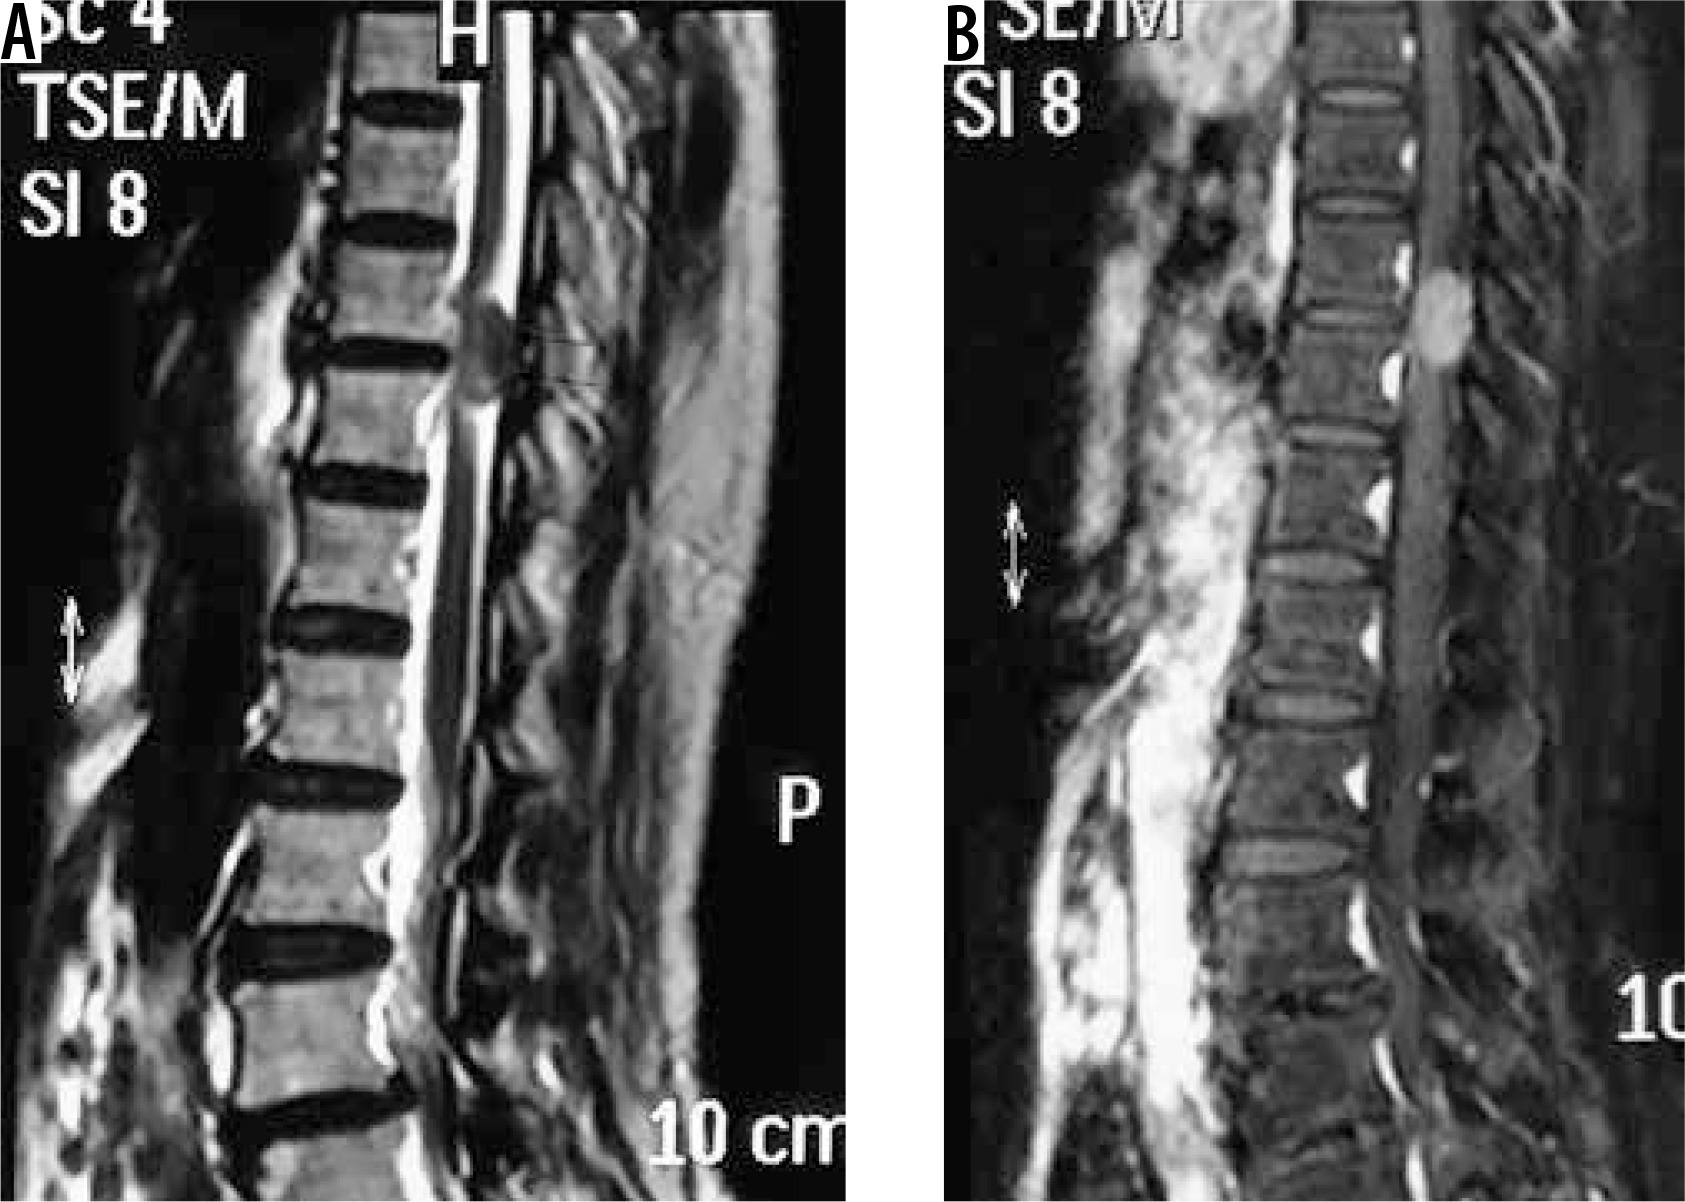

spinal canal meningioma: thoracic spinal canal meningioma is usually of the psammomatous variant (Figures 20 and 21) – differentials include other extramedullary spinal canal lesions;